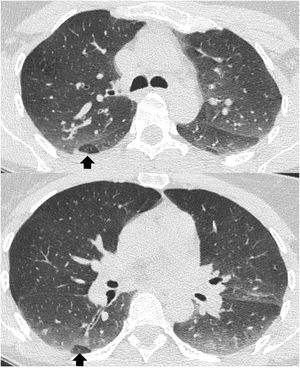

How to know if a good exhalation has been achievedThere is no accepted measure to determine whether a sufficient degree of expiration has been obtained on CT scan, with changes in tracheal morphology or increased lung attenuation being the most commonly used criteria. The posterior wall of the trachea, which is membranous in nature, moves backwards during inspiration, giving it the shape of the letter "O", while on expiration it moves forward, becoming straight (in the shape of the letter "D") or bulging slightly forward (Fig. 1A,B). However, it has been shown that in healthy volunteers the trachea can show a great variety of morphologies regardless of the degree of expiration reached, even remaining identical in both phases despite adequate expiration12 (Fig. 1C,D).

Variability of movements of the posterior tracheal membrane with respiration. In the patient on the upper images, posterior displacement is observed during inspiration (A) and anterior displacement during expiration (B), while in the patient on the lower images there are hardly any changes in the morphology of the trachea during inspiration (C) and expiration (D). The increase in lung density can be seen in the last picture.